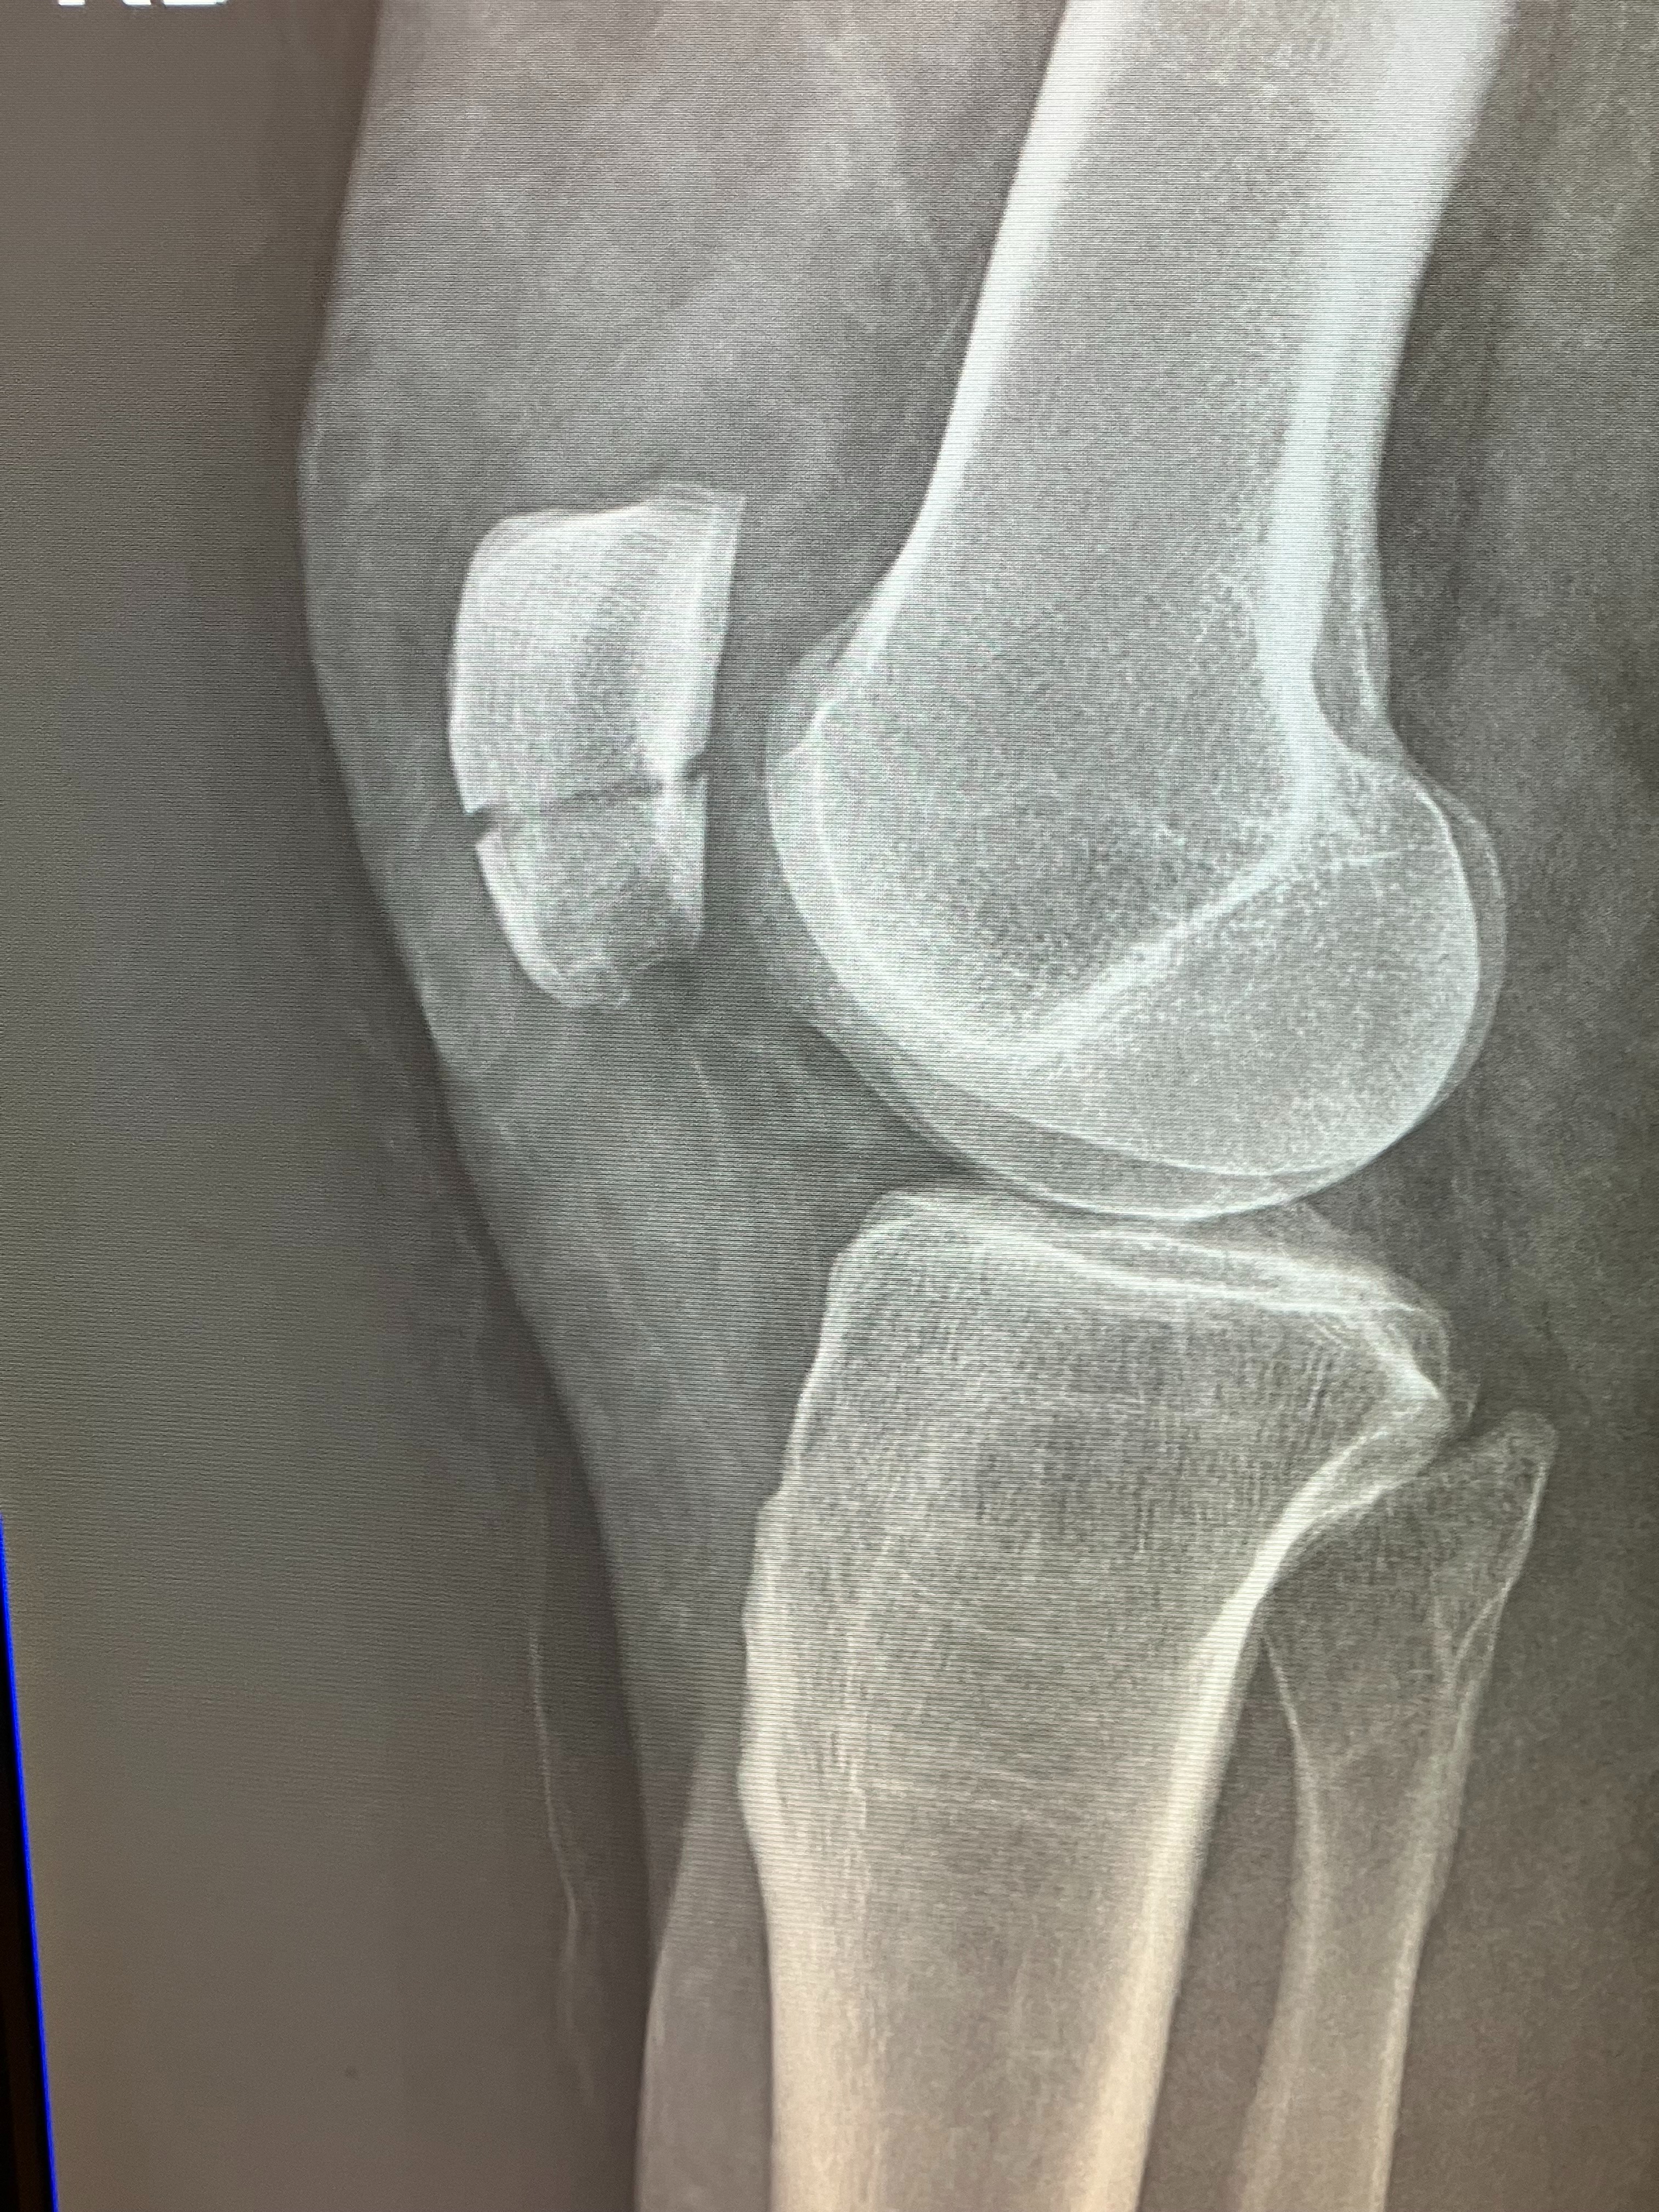

2025 left with a bang that forced me to focus on self care straight away in 2026. I slipped on black ice while walking to my building’s front door from my car and broke my kneecap on December 18th. The injury resulted in my inability to drive and work since the fall. I live alone away from friends and family who could assist me and I will not be able to return to work for at least another month. I have two dogs, Luca & Layla, who thank God are here with me. We are keeping each other company during this winter. I was previously doing work that would require more physical exertion than I am capable of and I am currently applying to positions that are easier on my body and more sustainable. I am also planning on moving closer to friends and family.